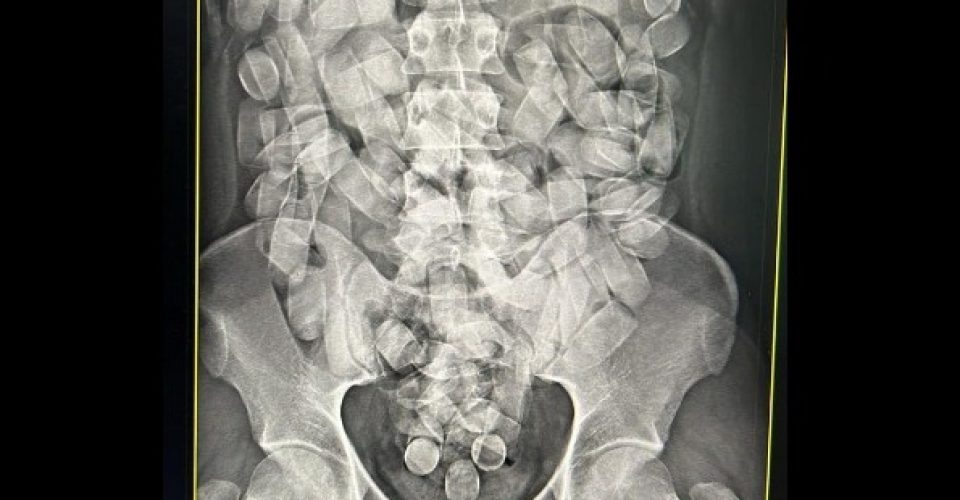

Homem é preso no aeroporto de Corumbá com 125 cápsulas de cocaína no estômago

No último domingo (19), policiais federais realizaram a prisão em flagrante de um homem enquanto tentava embarcar em um voo com destino a São Paulo.

Ele estava transportando cocaína em cápsulas no estômago. O caso ocorreu no aeroporto de Corumbá. O passageiro estava com 125 cápsulas ingeridas de cocaína. Segundo o registro policial, esta é a segunda prisão nesta semana no mesmo aeroporto realizada pela Polícia Federal.